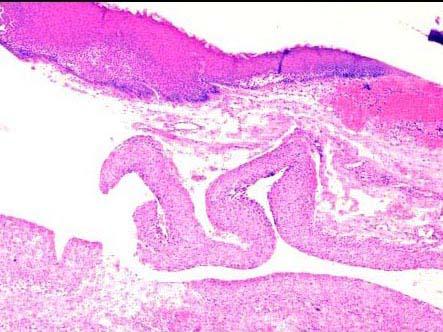

问题 患者,男,27岁,近日来声嘶伴吞咽疼痛,喉镜见声门上区有一灰白色囊状物,约1cm×0.6cm×0.5cm大小,活检镜下如图所示,正确的诊断是 ( )

选项 A.甲状舌骨囊肿 B.声带息肉 C.会厌囊肿 D.喉纤维瘤 E.喉神经纤维瘤

答案 C